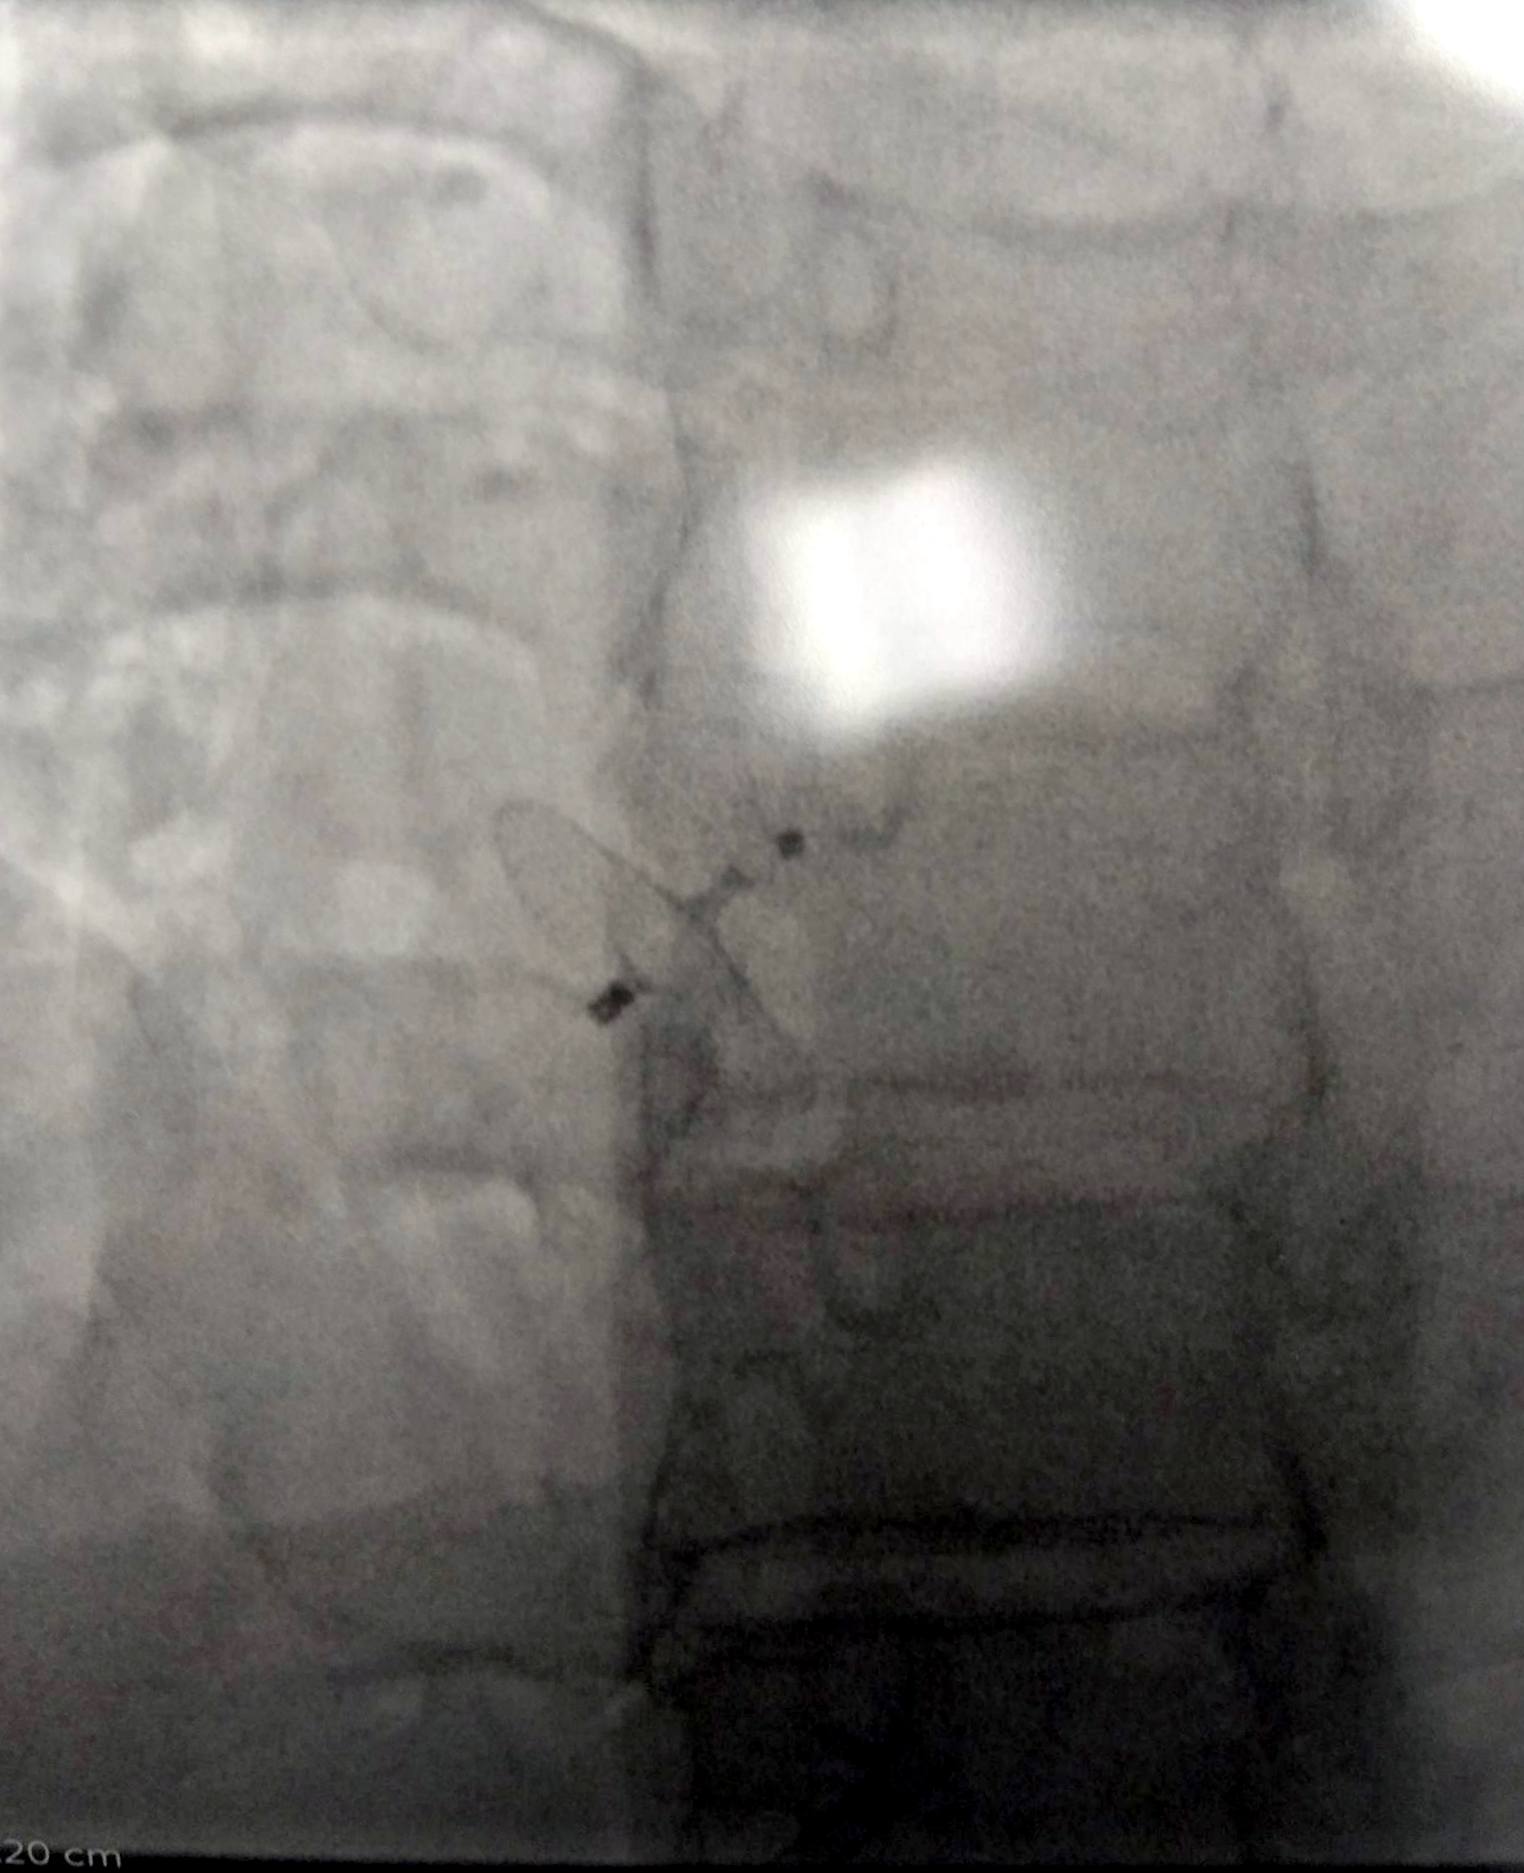

경피적 심방 중격 결손 폐쇄술은 카테터를 이용하여 심장의 구멍(결손)을 막는 시술 방법이다. 이는 가슴을 여는 외과적 수술 대신 혈관을 통해 접근하는 비교적 덜 침습적인 방법이다.[14] 시술은 보통 형광투시경 검사와 심장초음파 검사의 안내를 받으며 진행된다.

시술 과정은 다음과 같다. 먼저 대퇴 정맥을 통해 카테터를 삽입하여 심장의 우심방으로 보낸다.[14] 그 다음 카테터를 심방중격의 결손 부위를 통과시켜 좌심방으로 이동시킨다. 폐쇄 장치는 보통 두 개의 디스크 형태로 되어 있는데, 먼저 좌심방 쪽 디스크를 펼쳐 결손 부위에 고정시킨다. 이후 우심방 쪽 디스크를 펼쳐 중격 벽 양쪽에서 장치가 단단히 고정되도록 한다.[14] 난원공 개존증(PFO) 폐쇄의 경우, 이러한 시술이 약물 치료나 다른 의료 요법보다 향후 혈전색전증 위험을 줄이는 데 더 효과적인 것으로 알려져 있다.[14][50][51]

흔히 사용되는 폐쇄 장치 중 하나는 암플라처 중격 폐쇄 장치(Amplatzer Septal Occluder, ASO)이다. ASO는 다크론 직물로 채워진 약 0.01cm~약 0.01cm 두께의 니티놀(니켈-티타늄 합금) 와이어 메쉬로 만들어진 두 개의 원반이 4mm 허리로 연결된 형태이다. 장치 삽입은 비교적 간단하고 시술 후 잔여 결손이 남는 경우도 드물다.

경피적 폐쇄술은 외과적 수술에 비해 환자의 신체적 부담이 적고 입원 기간도 며칠 정도로 짧다는 장점이 있다.[79][74][80] 이 때문에 많은 의료기관에서 선호하는 치료법이다.[55] 여러 연구에 따르면, 특히 규모가 큰 병원에서 시행될 경우 비교적 안전하고 좋은 치료 결과를 보인다.[56][57]